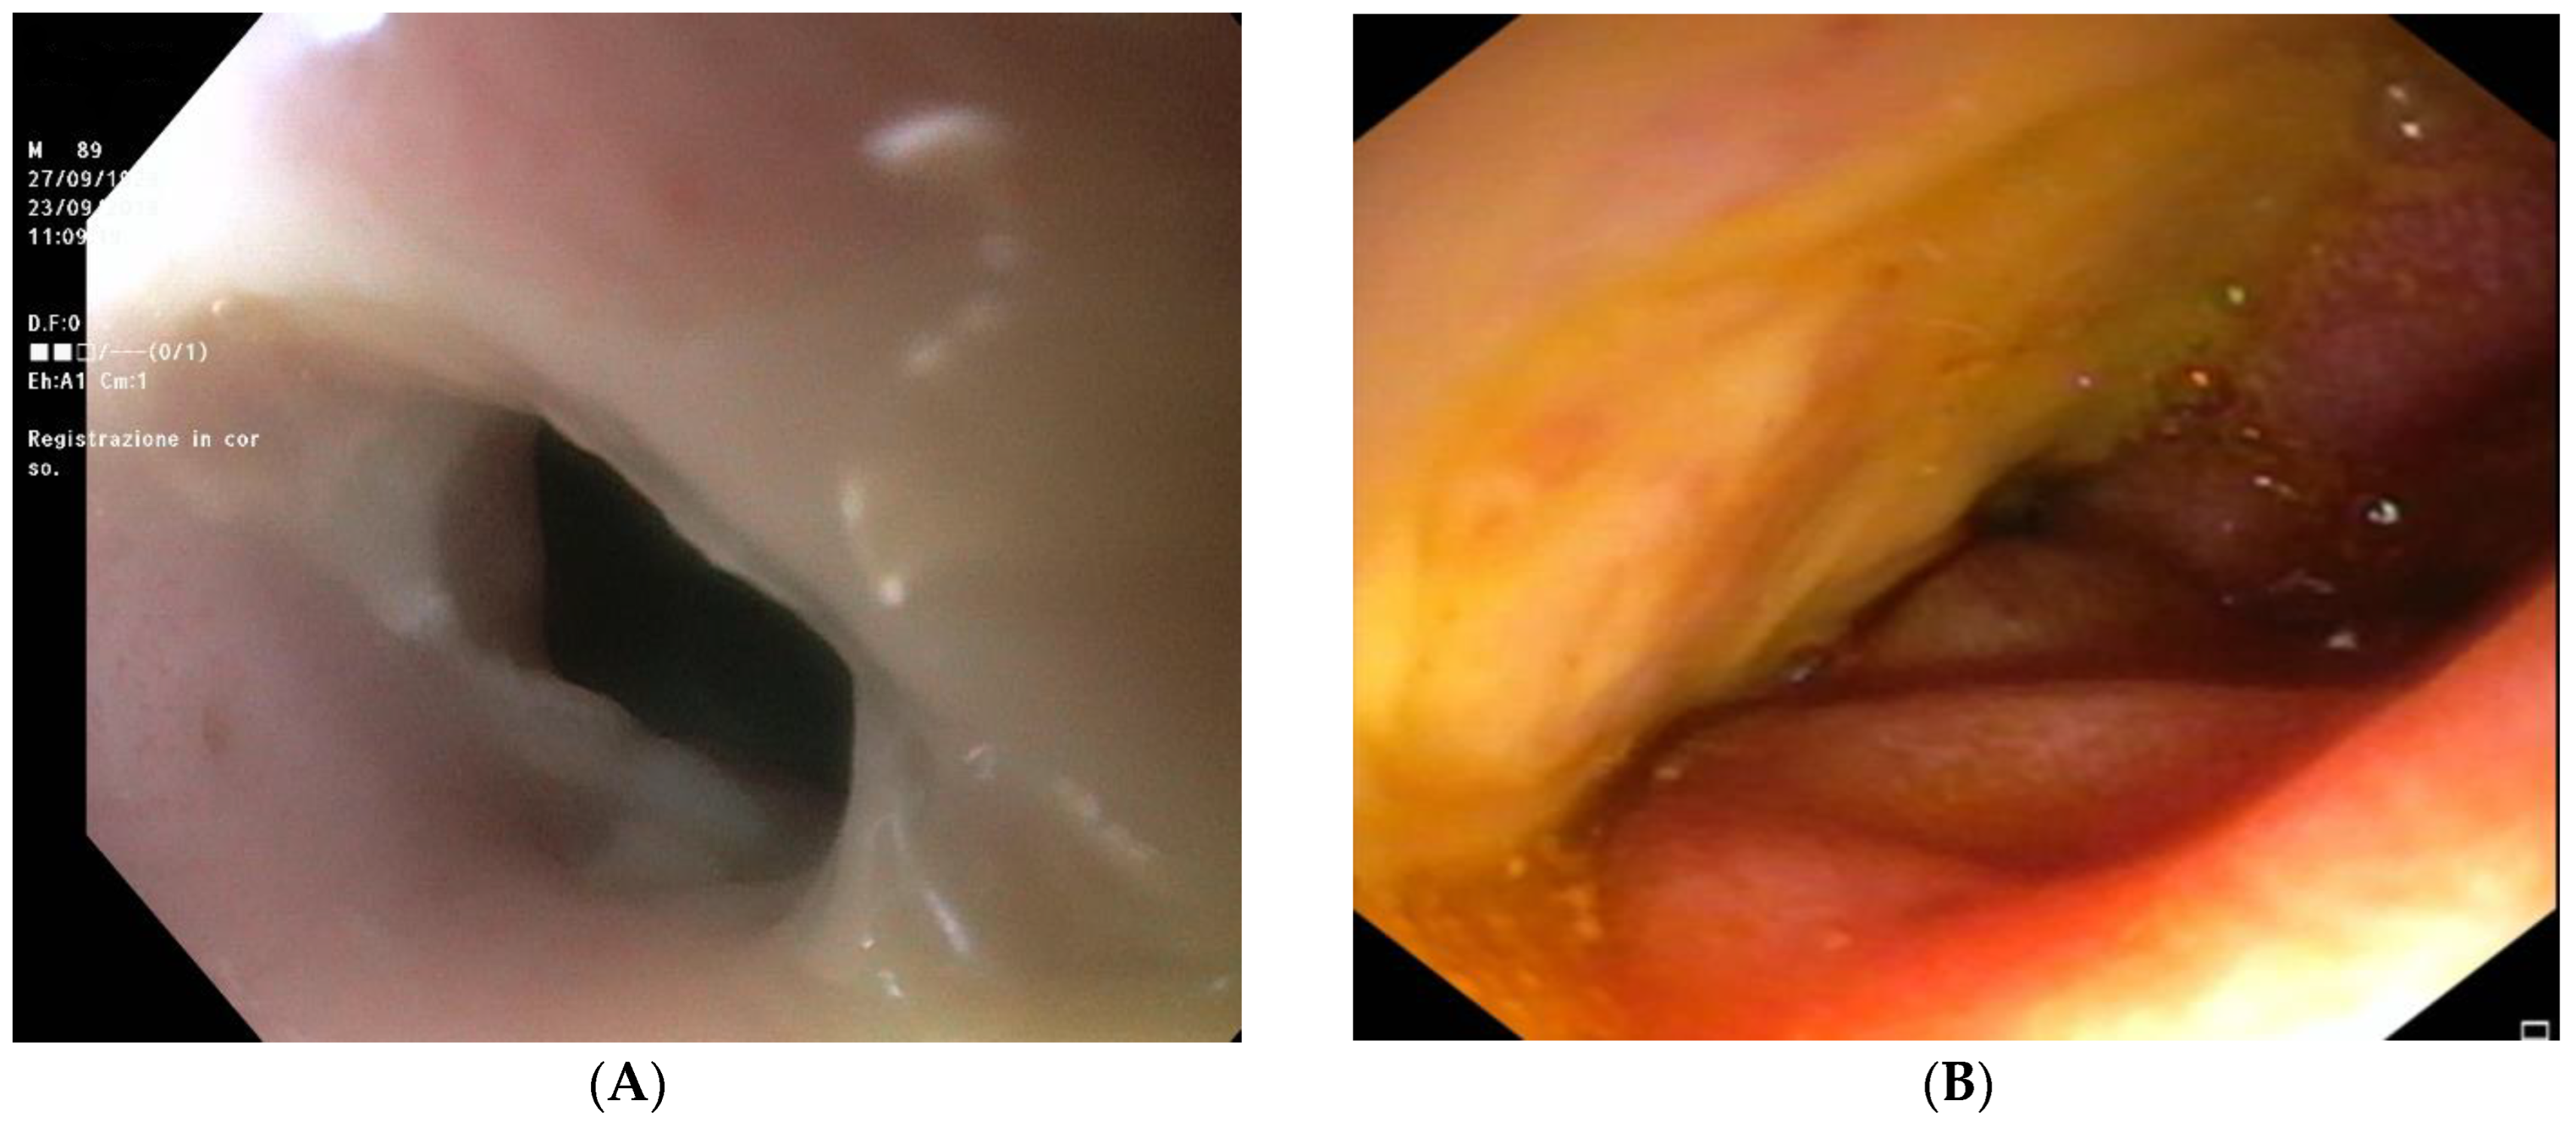

2.8. Further Diagnostic Work-Up

2.11. Outcome and Follow-Up